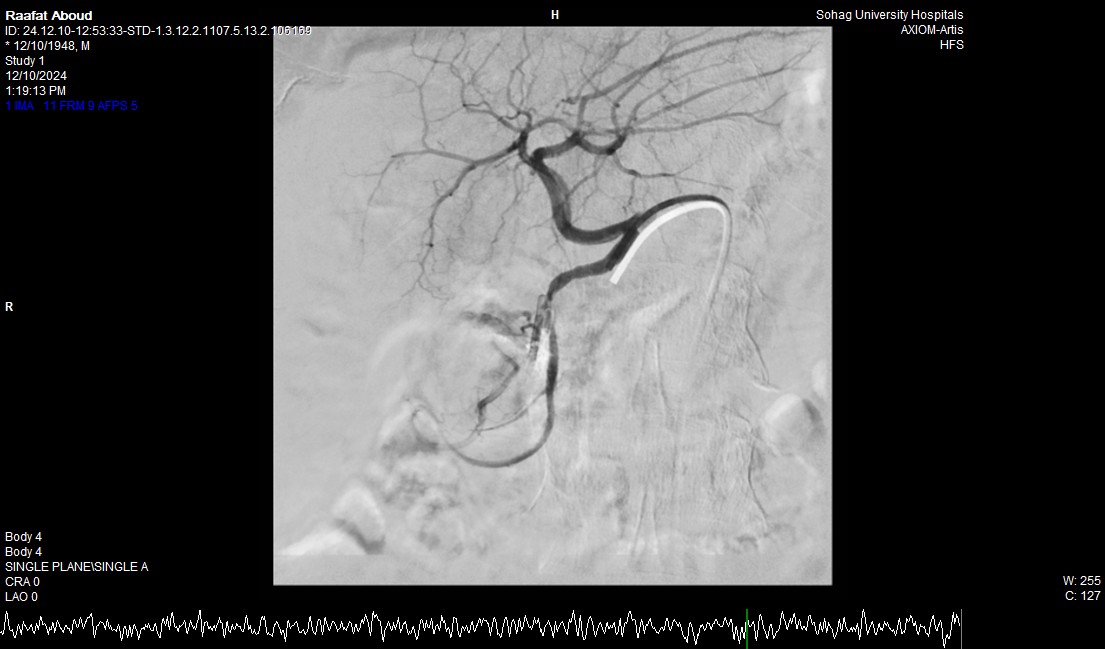

صرح الدكتور حسان النعماني رئيس جامعة سوهاج ان فريق طبي بوحدة الجهاز الهضمي والكبد بقسم الباطنة العامة ووحدة الاشعة التداخلية بقسم الاشعة نجح في انقاذ حياه مريض يبلغ من العمر ٧٥ عاماً له تاريخ مرضي ويعاني بقصور بوظائف الكلي وتليف بالكبد، حيث نجح الفريق في ايقاف نزف شرياني حاد من خلال إجراء التدخل السريع بإستخدام المنظار والقسطره الشريانيه العلاجيه بالاشعة التداخلية، مثمناً دور المستشفيات الجامعية في خدمة المرضي وما تمتلكه من الكوادر الطبية ذوي الخبرات التي تؤهلها للتعامل مع مثل هذه الحالات الطارئة باحترافية ومهارة فائقة.

وأضاف الدكتور أحمد كمال المدير التنفيذي للمستشفيات الجامعية انه بعد اجراء الفحوصات للمريض تبين وجود قرحة كبيرة بالاثني عشر وشريان نازف، حيث نجح الفريق في التحكم المبدئي بالنزيف عن طريق تركيب مشبك معدني بالمنظار وحقن للقرحة النازفة، ثم تم استدعاء فريق أطباء وحدة الاشعة التداخلية علي الفور وتم عمل غلق للشريان النازف بشكل عاجل من خلال جهاز القسطرة.

وذكر الدكتور نايل عبد الحميد رئيس قسم امراض الباطنه ان هذا التدخل الطارئ لايقاف النزيف من خلال المنظار او من خلال غلق الشريان بواسطه الاشعة التداخلية جنب المريض من التعرض للحل الجراحي في هذا العمر، مشيراً الي ان المريض الآن في حالة مستقرة حيوياً وتوقف تام للنزيف وتحسن لوظائف الكلي والكبد وتم خروجه من وحدة الرعاية المتوسطة للمتابعة بالقسم الداخلي

وأوضح الدكتور محمد زاكي رئيس قسم الأشعة أن مثل هذه الحالات تعد من الطوارئ الطبية الخطيرة والتي تستوجب عمل قسطره شريانية عاجلة لغلق الشرايين النازفه مشيراً أن وحدة الأشعة التداخلية تم تزويدها بجهاز أشعه محوري متقدم لاجراء مثل هذه الحالات، وأن هذا النجاح هو نتيجة لتعاون أقسام المستشفي مع وحدة الأشعة التداخليه لتقديم خدمة مميزه للمرضي.